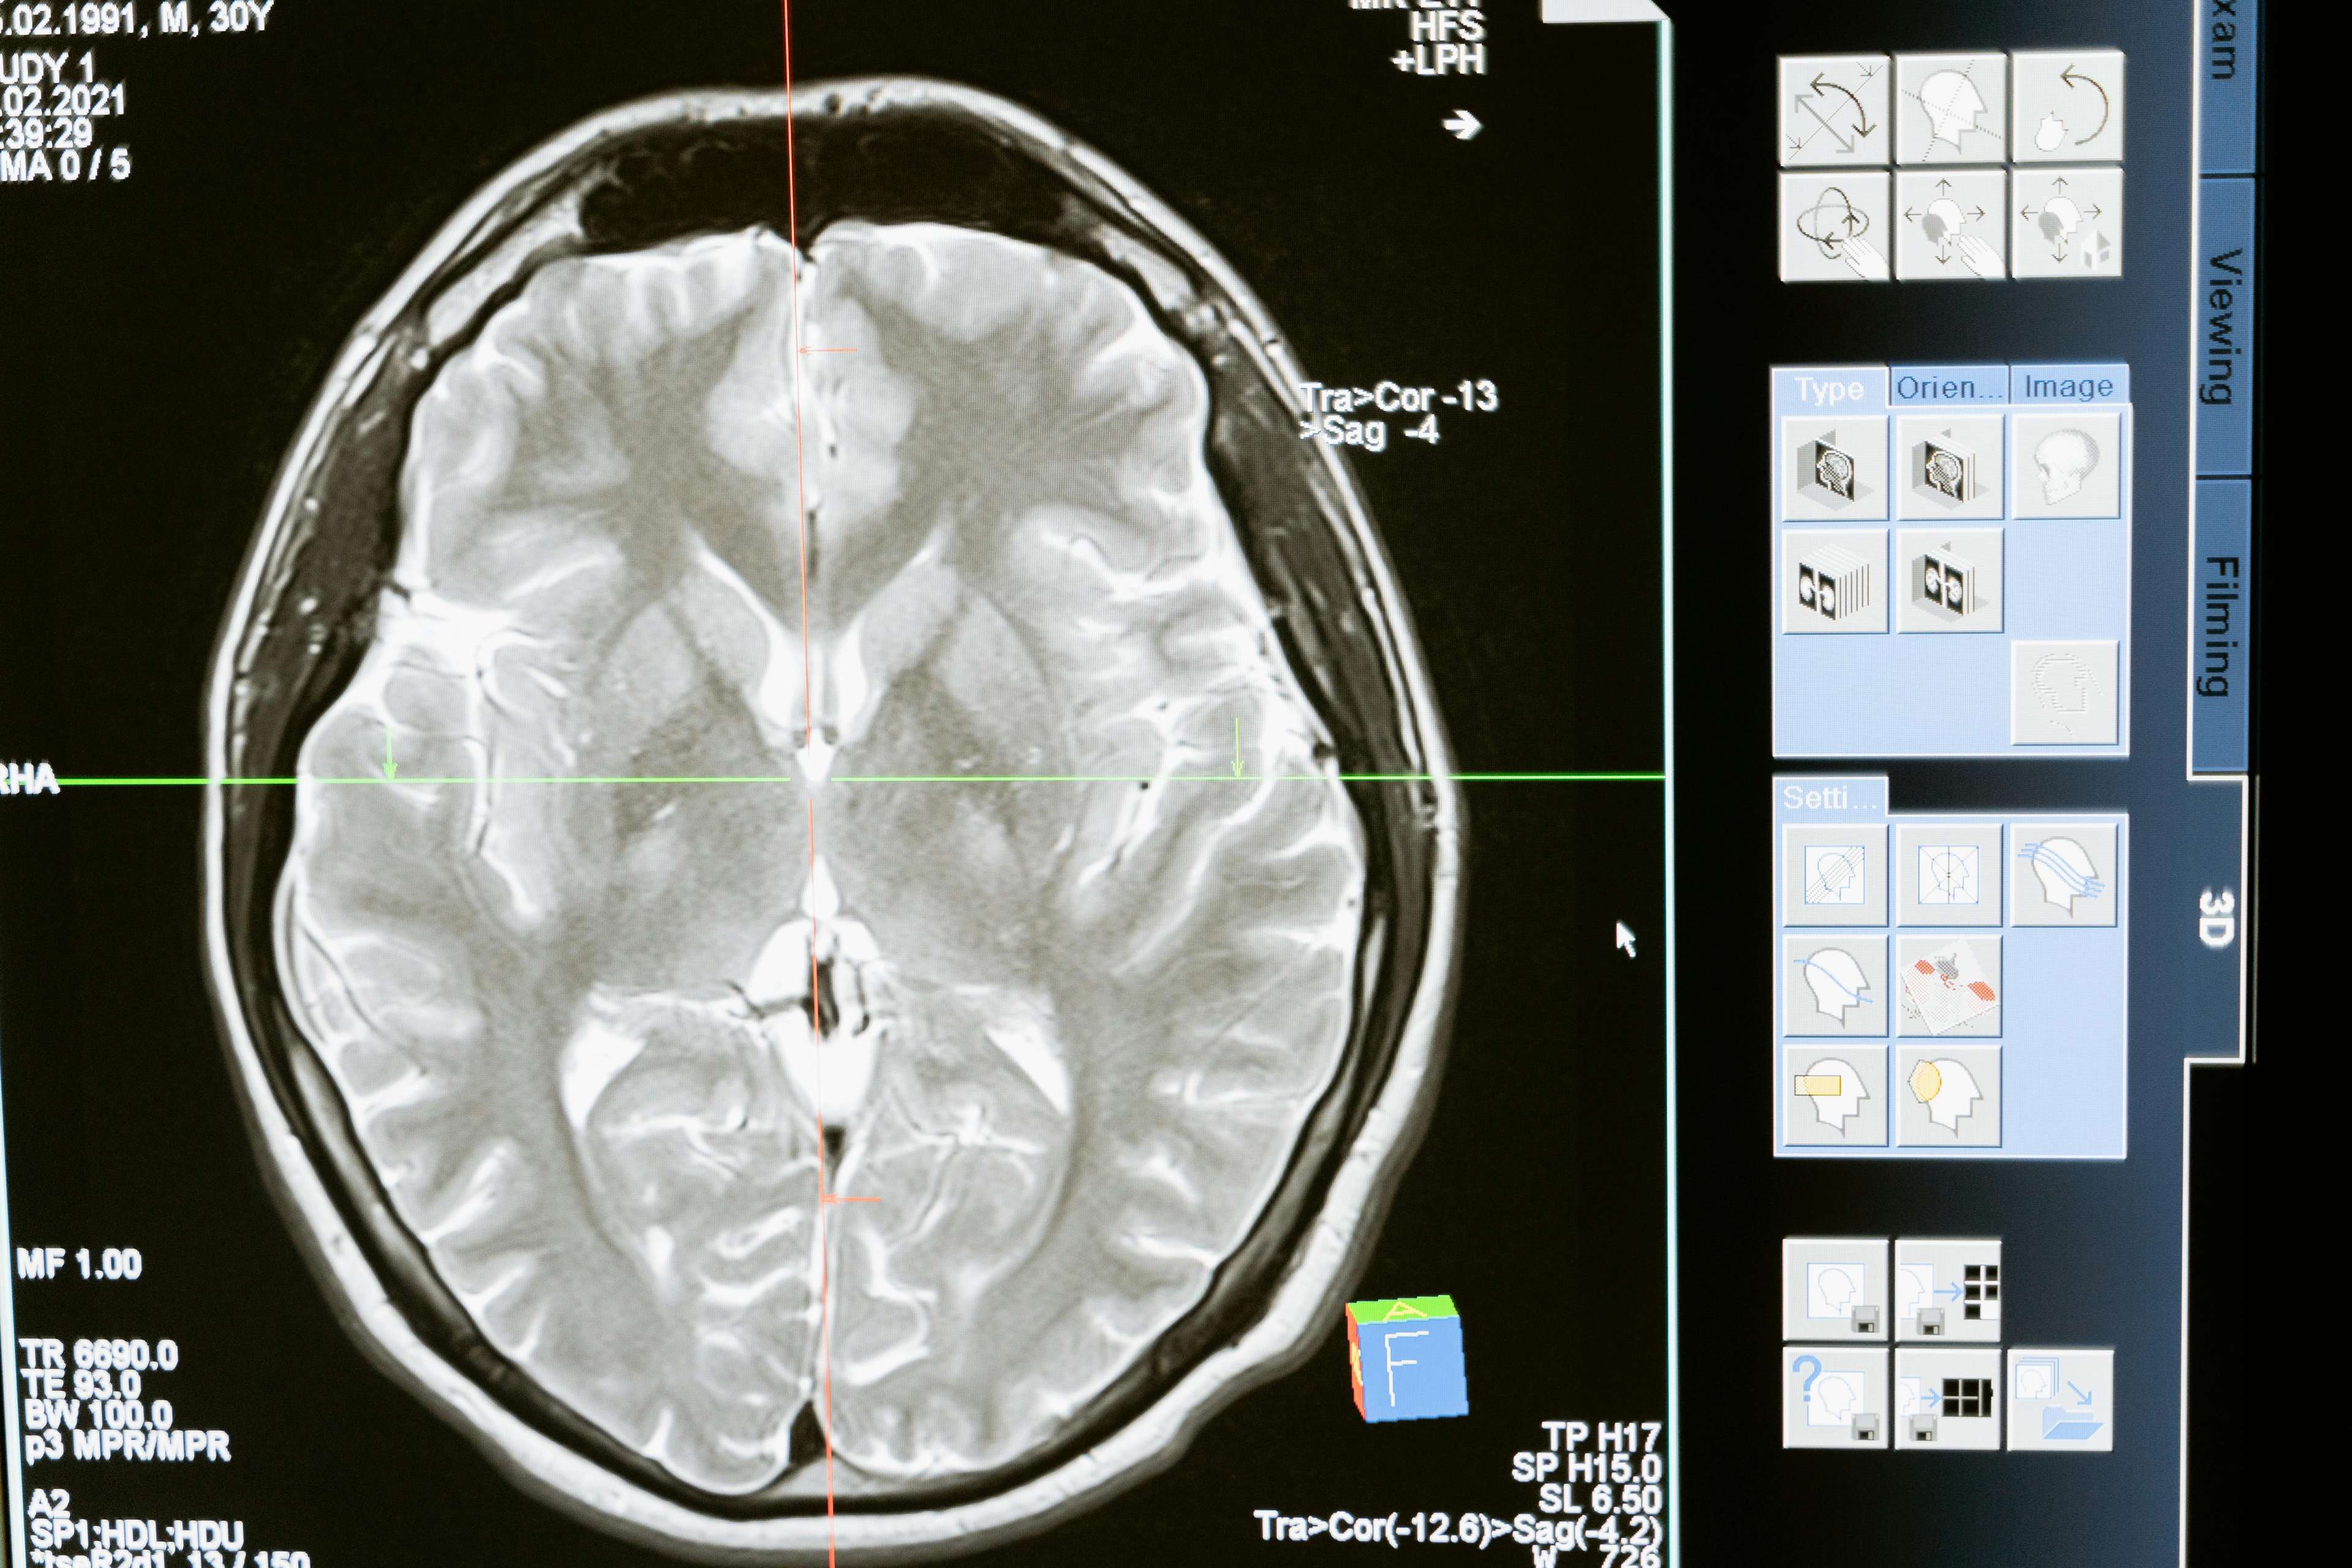

DBS የኤሌክትሪክ ግፊትን ወደ ተወሰኑ የአንጎል አካባቢዎች የሚልክ መሳሪያን በመትከል ለተለያዩ የነርቭ በሽታዎች ምልክቶች ተጠያቂ የሆኑትን የነርቭ ግንኙነቶችን በተሳካ ሁኔታ "ማደስ" የሚያካትት የቀዶ ጥገና ሂደት ነው. ይህ የፈጠራ ህክምና እንደ ፓርኪንሰን በሽታ፣ ዲስቶንሲያ፣ ኦብሰሲቭ ኮምፐልሲቭ ዲስኦርደር (OCD) እና የሚጥል በሽታ እና ሌሎችም ባሉባቸው ግለሰቦች ላይ የሚደርሰውን ስቃይ ለመቅረፍ ትልቅ እገዛ አድርጓል. የእነዚህን ሁኔታዎች ዋና መንስኤ በማነጣጠር ዲቢኤስ የሞተርን ተግባር በእጅጉ እንደሚያሻሽል፣ መንቀጥቀጥን እንደሚቀንስ እና አጠቃላይ የህይወት ጥራትን እንደሚያሳድግ ታይቷል.

የአንጎልን ሚስጥሮች መክፈት

ስለዚህ፣ ዲቢኤስ አስማቱን እንዴት ይሰራል. አየህ, አንገታችን በኤሌክትሪክ ግፊቶች አማካይነት እርስ በእርስ ከሚገናኝባቸው ውስብስብ የነርቭ ኔትወርክ ጋር ተያያዥነት አላቸው. የነርቭ ሕመም ባለባቸው ግለሰቦች እነዚህ ግፊቶች ሊስተጓጉሉ ይችላሉ, ይህም ወደ መገናኛው መበላሸት እና በመጨረሻም የሕመም ምልክቶች መታየትን ያስከትላል. DBS ኤሌክትሪክ ግፋቶችን ለአንጎል ለተወሰኑ የአንጎል አካባቢዎች እንዲልክ, ውጤታማ በሆነ መንገድ "ዳግም የሚገኘውን" ዳግም ወደ የአንጎል ለስላሳ ሥነ-ምህዳሮች ቀሪ ሂሳብን መልሶ ለማቋቋም ችሎታን በመልቀቅ ይሠራል.